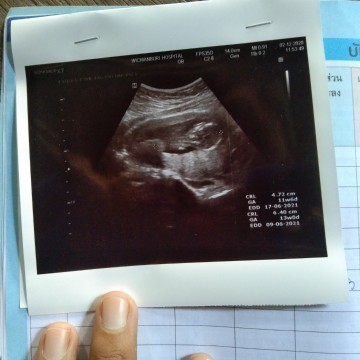

น้องเพศชายค่ะได้ 12 สัปดาห์ 🥰

ท้อง2จร้า10วีค4วัน รอลุ้นค่ะ😊